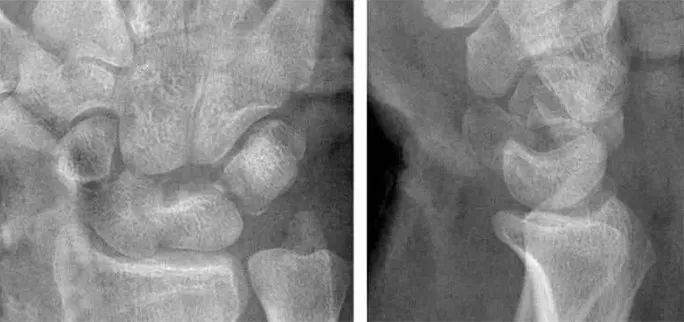

Case 分析

1.月骨-三角骨间隙平行关系缺失致掌骨弧线I and II中断。

2.月骨和舟骨平行,而与其他腕骨不平行。

3.舟骨缩短提示向掌侧倾斜。

4.月骨平行于舟骨,其三角形状提示为掌侧倾斜所致。

5.近排腕骨不是一个整体,因为弧线I中断。

诊断:掌屈不稳伴月骨-三角骨关节脱位